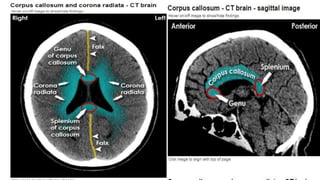

GREY VS WHITE

• The CNS has two kinds of tissue: grey matter and white matter.

• Grey matter contains most of the brain's neuronal cell bodies.[outside]

• White matter is made of axons connecting different parts of grey matter to

each other[inside]

CordBrain

White and grey mater on CT

White and grey mater on MRI

T1 T2